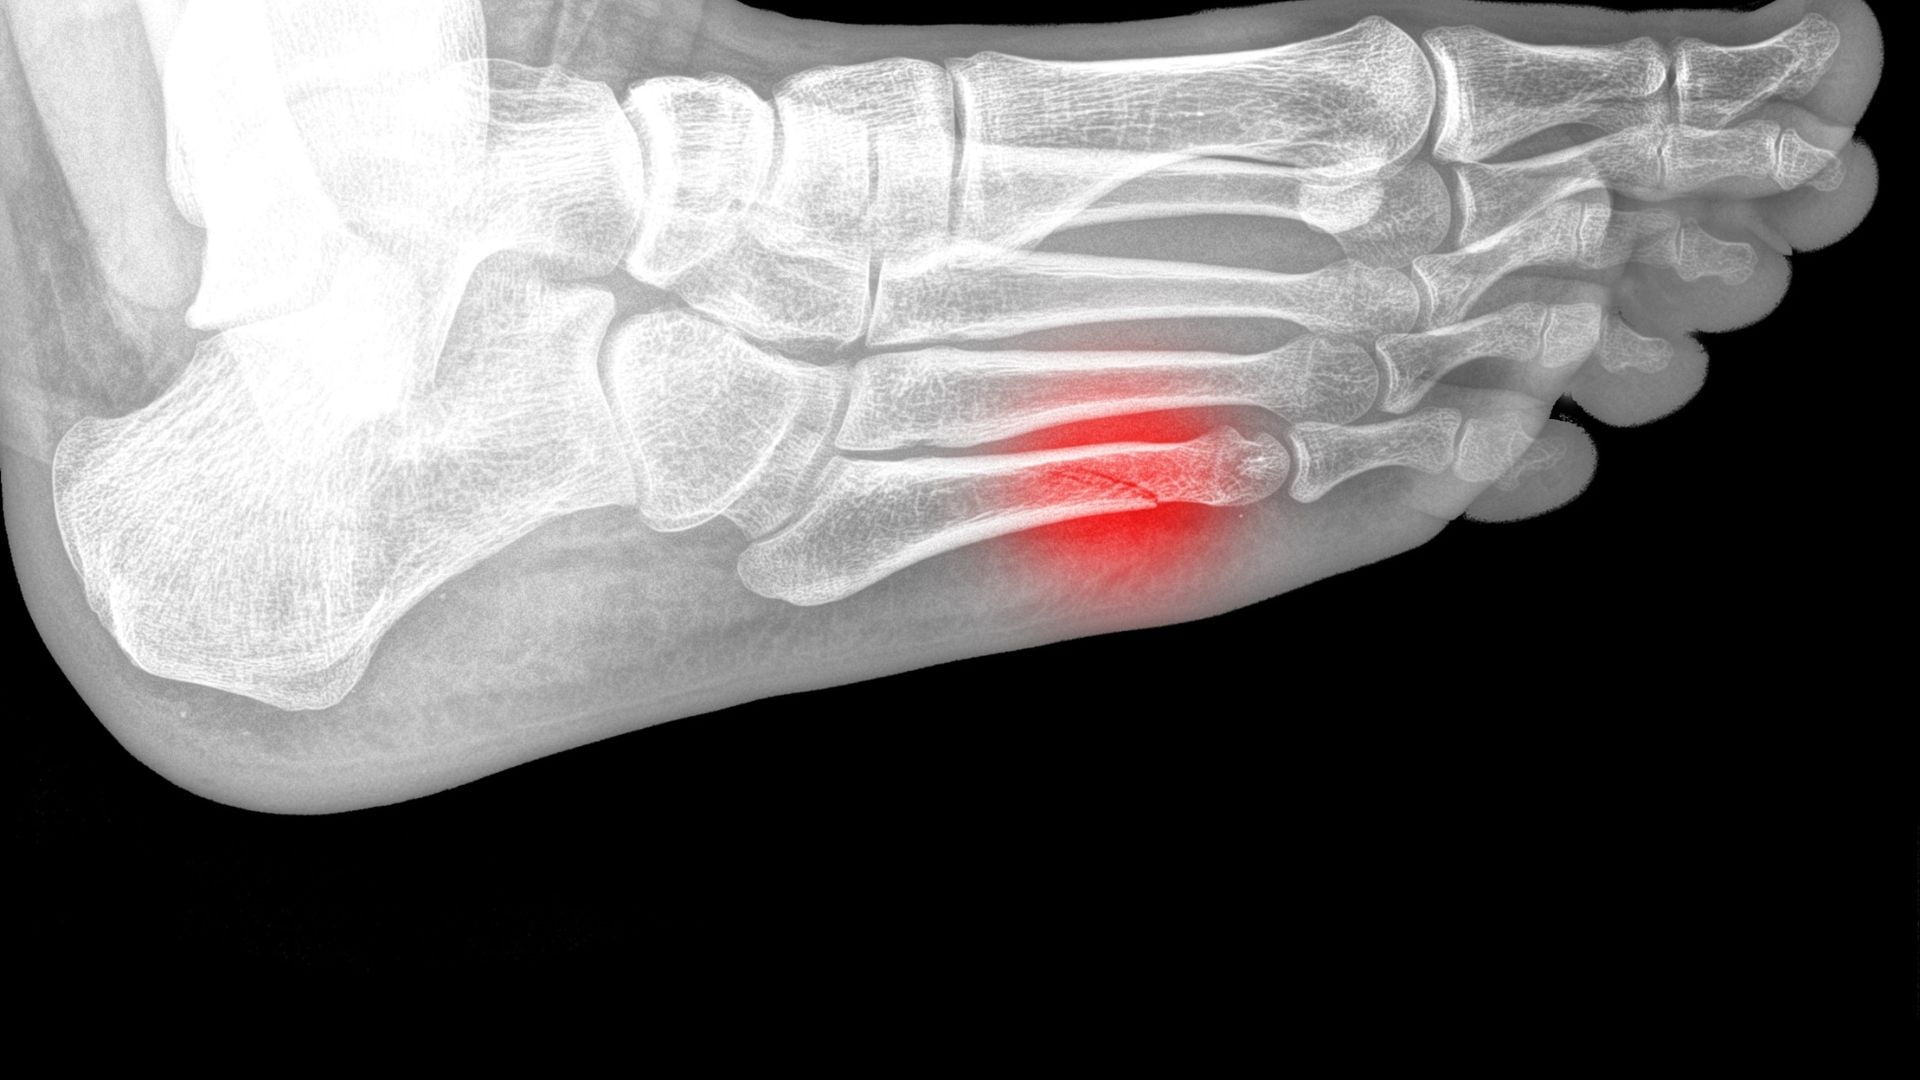

¿Qué es el quinto metatarsiano y cómo se fractura?

El quinto metatarsiano es el hueso que está antes del dedo chiquito del pie. Su fractura suele estar asociada a una carga excesiva repetitiva o en mecanismos parecidos a los que ocasionan el esguince de tobillo.